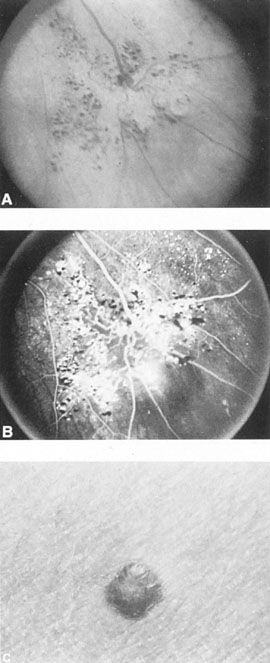

Approximately 100 years ago, Terson recorded the occurrence of vitreous hemorrhage after spontaneous subarachnoid bleeding. Such ocular hemorrhage is believed to result from transmission of intracranial pressure through the subarachnoid communication between the optic nerve sheath and the intracranial cavity, with subsequent nerve sheath dilation and rupture of dural and bridging vessels (Fig. 2). Intraocular hemorrhage is possibly the result of retinal venous hypertension brought on by obstruction of both the central retinal vein and the retinochoroidal anastomoses. Kuhn et al3 have reviewed Terson's syndrome, including the role of pars plana vitrectomy; these authors noted the high incidence of preceding coma, and the efficacy of surgical intervention in visual recovery.

Fig. 2. Terson's syndrome. Multiple preretinal hemorrhages accompanying subarachnoid bleeding.